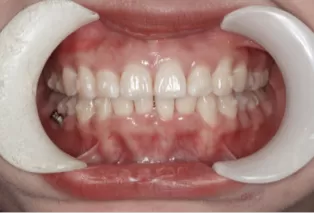

Female, 25 years old. Chief complaint: protruding and misaligned teeth, requiring orthodontic treatment.

Intraoral photos

Before Treatment